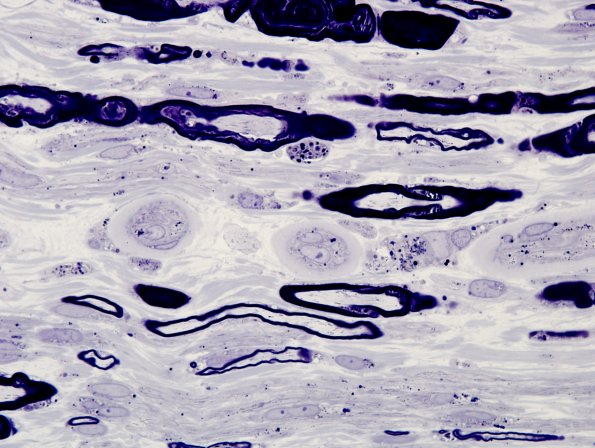

Washington University Experience | PERIPHERAL NEUROPATHY | 17 TOXIC NEUROPATHIES | Amiodarone | 2A11 Amiodarone neuropathy (Case 2 Plastic 5

Inclusions are seen in Schwann cells of degenerating and intact axons. (plastic section)